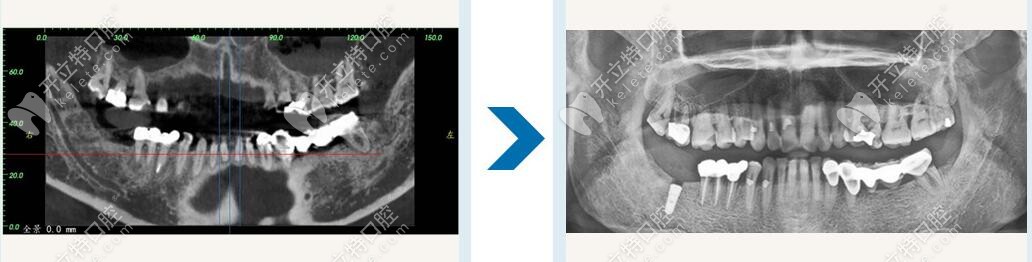

南寧柏樂口腔種植牙修復(fù)

Locator就是低平的牙槽骨上種植2-4顆種植體,通過種植體外接扣鎖的形式增加半口義齒的固位,一般種植后要讓種植體穩(wěn)定3-6月,然后在上外接裝置前一個月做半口義齒修復(fù),試戴一月,再進行連接修復(fù)。